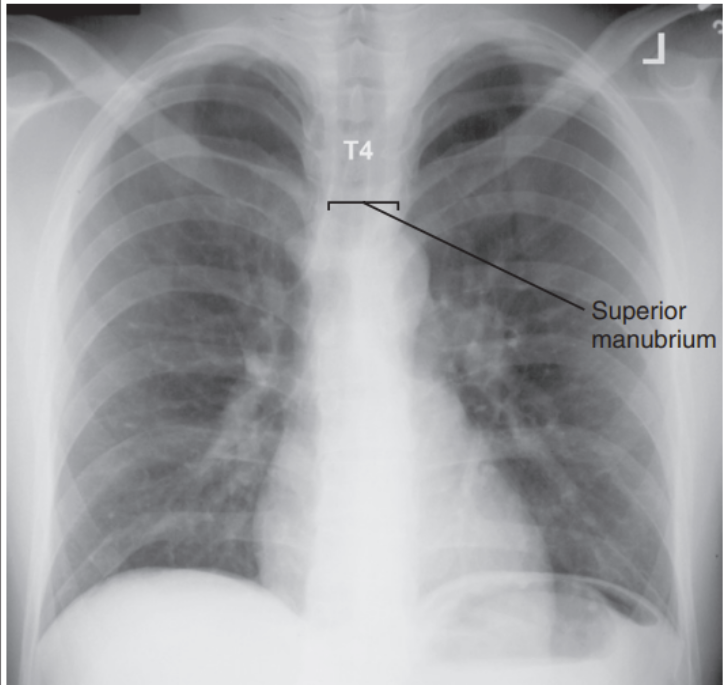

Superior midcoronal tilt anteriorly

Manubrium at 5th vertebrae

Patient’s superior midcoronal is tilted anteriorly